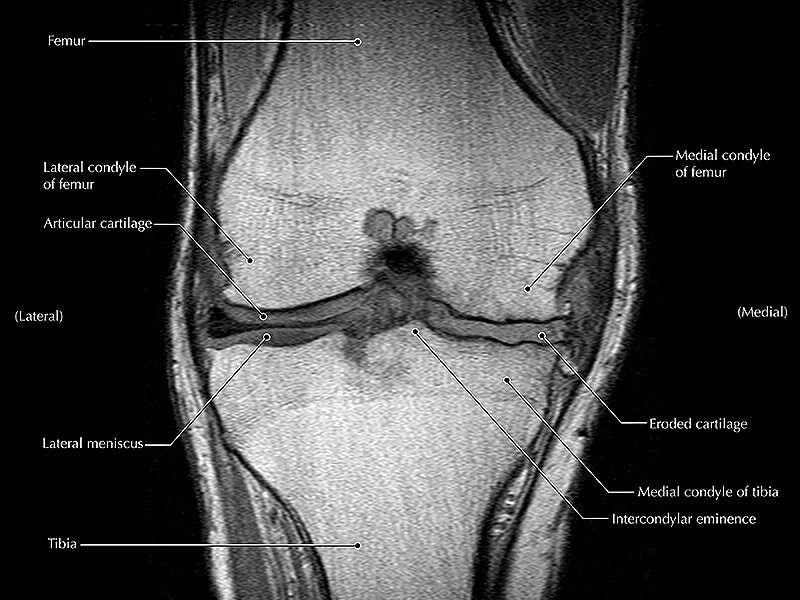

Мрт при боли в суставах